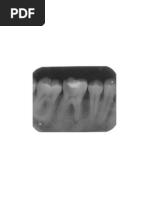

c. Angular 6. Apakah klasifikasi impaksi molar ketiga rahang bawah

d. Ushaped pada gambar di samping?

e. Semilunar a. kelas I C mesioangular

b. kelas I A mesioangular

3. Seorang perempuan usia 25 tahun datang ke rumah sa c. kelas I A horizontal

kit mengeluhkan adanya pembengkakan pada gusi depan d. kelas II A horizontal

rahang atasnya sejak 5 hari yang lalu. Pasien ingin giginy

e. kelas II A mesioangular

9. Pasien perempuan datang dengan keluhan nyeri pada

sebagian untuk ukuran mesio-distal mahkota gigi molar

rahang bawah sebelah kiri. Pasien telah melakukan foto

tiga yang impaksi, dan puncak tertinggi molar ketiga

panoramik. Apakah diagnosis dari gambar di bawah ini

berada dibawah servikal molar kedua. Apakah Klassifikasi

menurut klasifikasi impaksi pell and gregory?

A. Klas IB mesioangular

B. Klas IIB vertikal A. Operkulektomi

C. Klas IA horizontal B. Odontektomi

D. Klas IIIC horizontal C. Alveolektomi

E. Klas IIC vertical D. Bedah flap